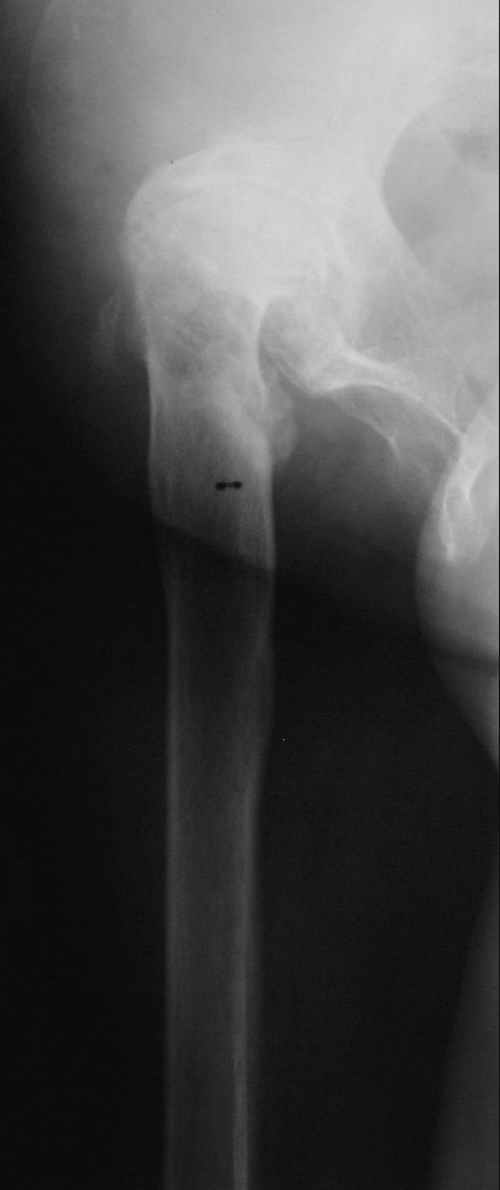

Уважаемые коллеги! Хотелось бы услышать Ваше мнение относительно тактики лечения данной пациентки. Пациентка 1953 г.р. поступила в клинику с диагнозом: "Деформирующий артроз в неоартрозе III ст. между головкой правого бедра и правой подвздошной костью, исход открытого вправления врождённого вывиха правого бедра. АВНГБ слева III-IV ст., коксартроз слева IIIст.Остеобластокластома левой седалищной кости."Из анамнеза: в возрасте 14 лет - открытое вправление врождённого вывиха правого бедра. В 1980 г. остеотомия, дистракционный остеосинтез правой бедренной кости.Зимой 2003г. обнаружена ОБК левой седалищной кости, получила курс лучевой терапии. В настоящее время данных за прогрессирование патологического очага нет. Пациентка поступила для эндопротезирования правого тазобедренного сустава. Учитывая наличие вальгусной деформации правого бедра и костей правой голени, возник вопрос, что выполнять в первую очередь - эндопротезирование, или же корригирующие остеотомии с исправлением оси конечности? Мнения коллег разделились.Заранее благодарны за помощь.

С отведением у пациентки проблемы - 0 град., приведение до 30 град, сгибание/разгибание=140/150 град., внутр. ротация 0 град., наружная ротация 20 град. Относительное и ортопедическое укорочение правой нижней конечности всего 1 см.(в 1980г. удлинение правого бедра на 4 см.). Имеются признаки остеохондроза дисков поясничного отдела позвоночника.

Учитывая отсутствие выраженной фиксированной приводящей контрактуры, рассматривали вариант первичной коррекции вальгусной деформации конечности.

Второй рассматриваемый вариант - эндопротезирование правого тазобедренного сустава с низведением и коррекцией деформации на уровне проксимального отдела бедра. Вторым этапом - коррекция вальгусной деформаци голени.